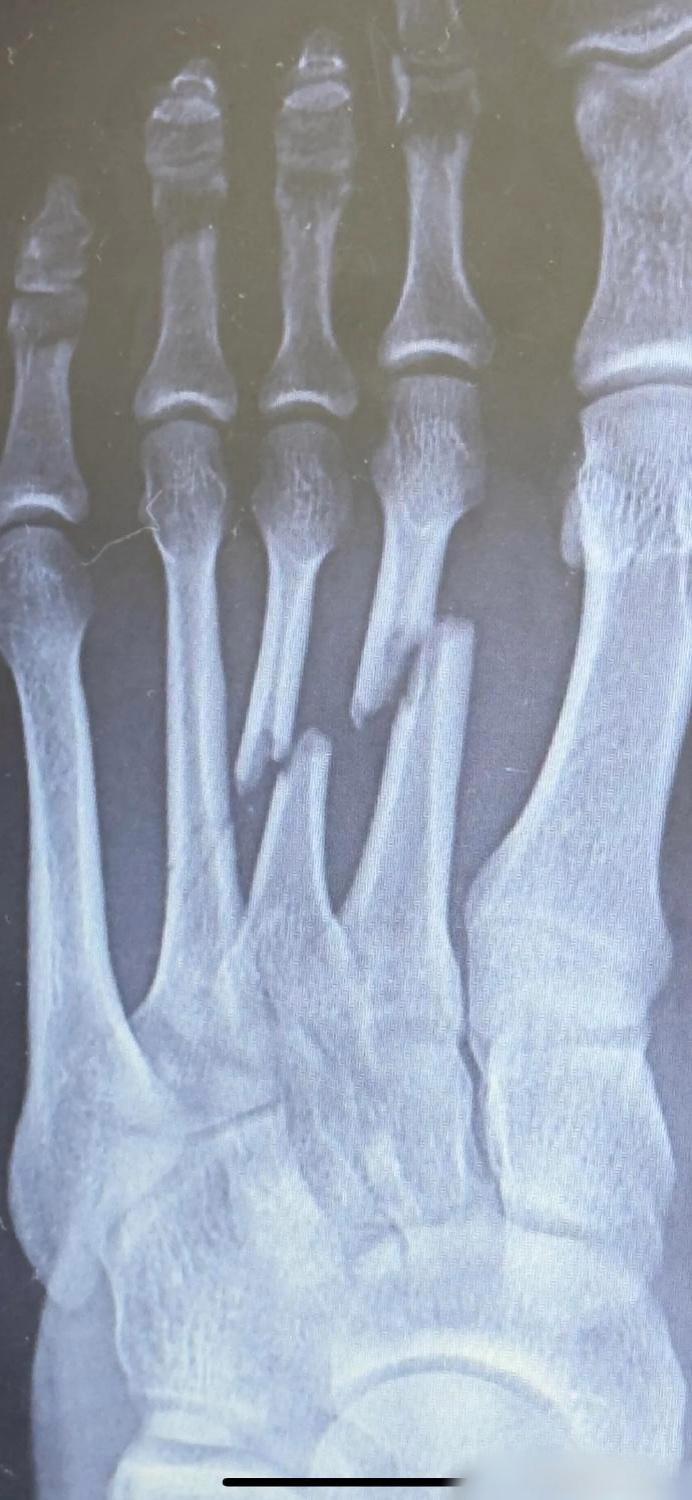

人体的治愈力,骨折后的3个月是这样的!